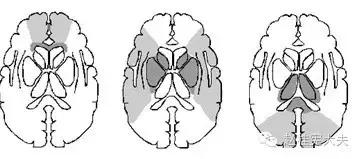

患者的磁共振影像不符合脑血管病的血供分布,跨了大脑中动脉和大脑后动脉范围,且病灶偏皮层分布。大脑前、中、后动脉血供分布(横断面)见下图